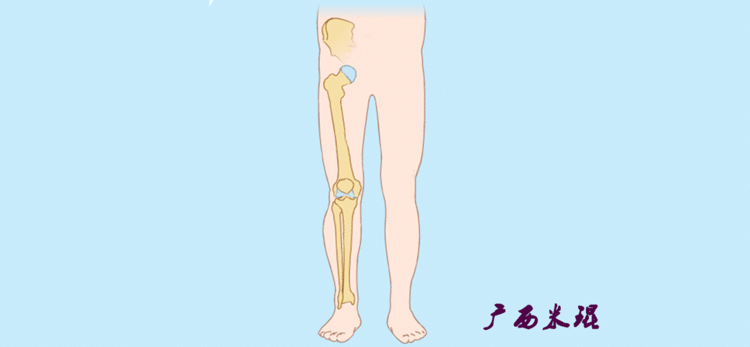

1、判定有无畸形下肢的畸形定义为生理轴线的偏移。关节角和轴线在冠状面、矢状面和横断面上可发生病理改变,并引起整个下肢的对线异常。

最常见的下肢畸形发生于冠状面,即膝内外翻畸形,冠状面的对线异常通过应用“对线异常检验”进行分析,机械轴的偏移(MAD)表现为对线异常。

膝内翻是指下肢力线通过膝关节中心点内侧,距中点2mm以上,偏内超过15mm为显著膝内翻。膝外翻是指下肢力线通过膝关节中心点外侧,距中点2mm以上,偏外超过10mm为显著膝外翻。